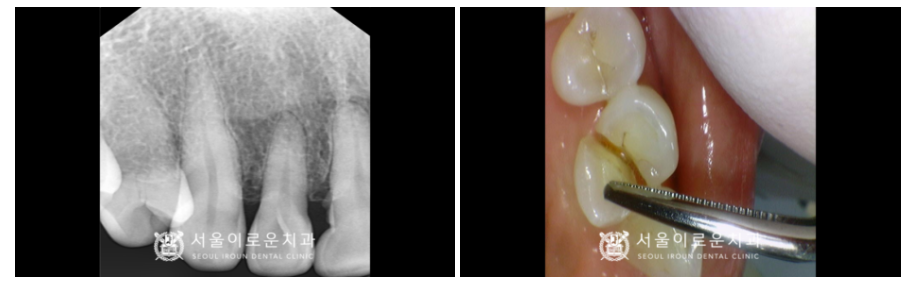

x-ray 상으로는 크랙 라인이

또렷하게 관찰되지는 않지만

구내에서 확인하였을 때

상당히 깊게 크랙이

진행된 것으로 보였으며

타진 반응에도 통.증이 있었습니다.

안타깝게도 치아가 둘로 쪼개져

예후가 좋지 않아

발치를 해야 하는 상황이었답니다. (ㅠㅠ)

왼쪽 치경부 마모증 부위에

레진 수복을 진행해 드렸습니다.